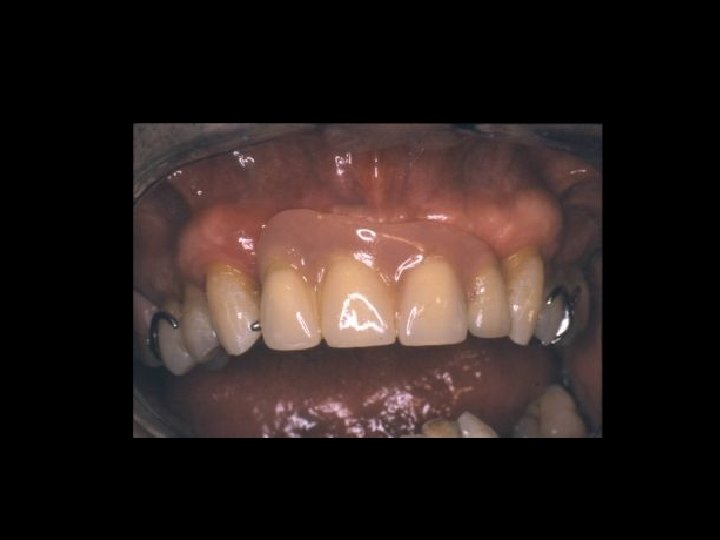

Responsabilità Garanzia di mezzi Ø Garanzia di risultato Ø Scelta del tipo di trattamento Ø Ø Condizioni denti Ø Condizioni delle mucose Ø Condizioni delle ATM Ø Preparazione dei denti pilastro Ø Prospettive di risultato estetico Ø Prospettive di risultato nel tempo Ø Caratteri del manufatto